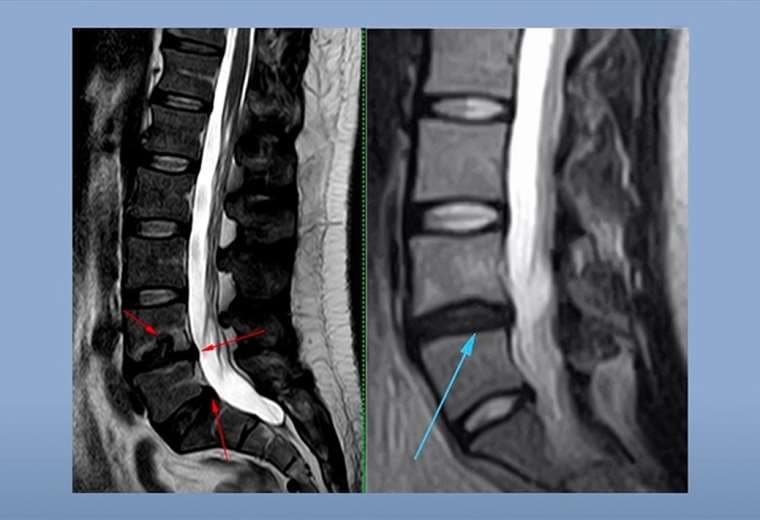

El dolor de espalda normalmente es asociado a personas mayores. Sin embargo, las personas jóvenes en sus 25, 30 o 40 años también podrían experimentar dolor en la espalda baja.

Este tipo de dolor puede ser debilitante y afectar su calidad de vida, por lo que hay que prestarle atención.